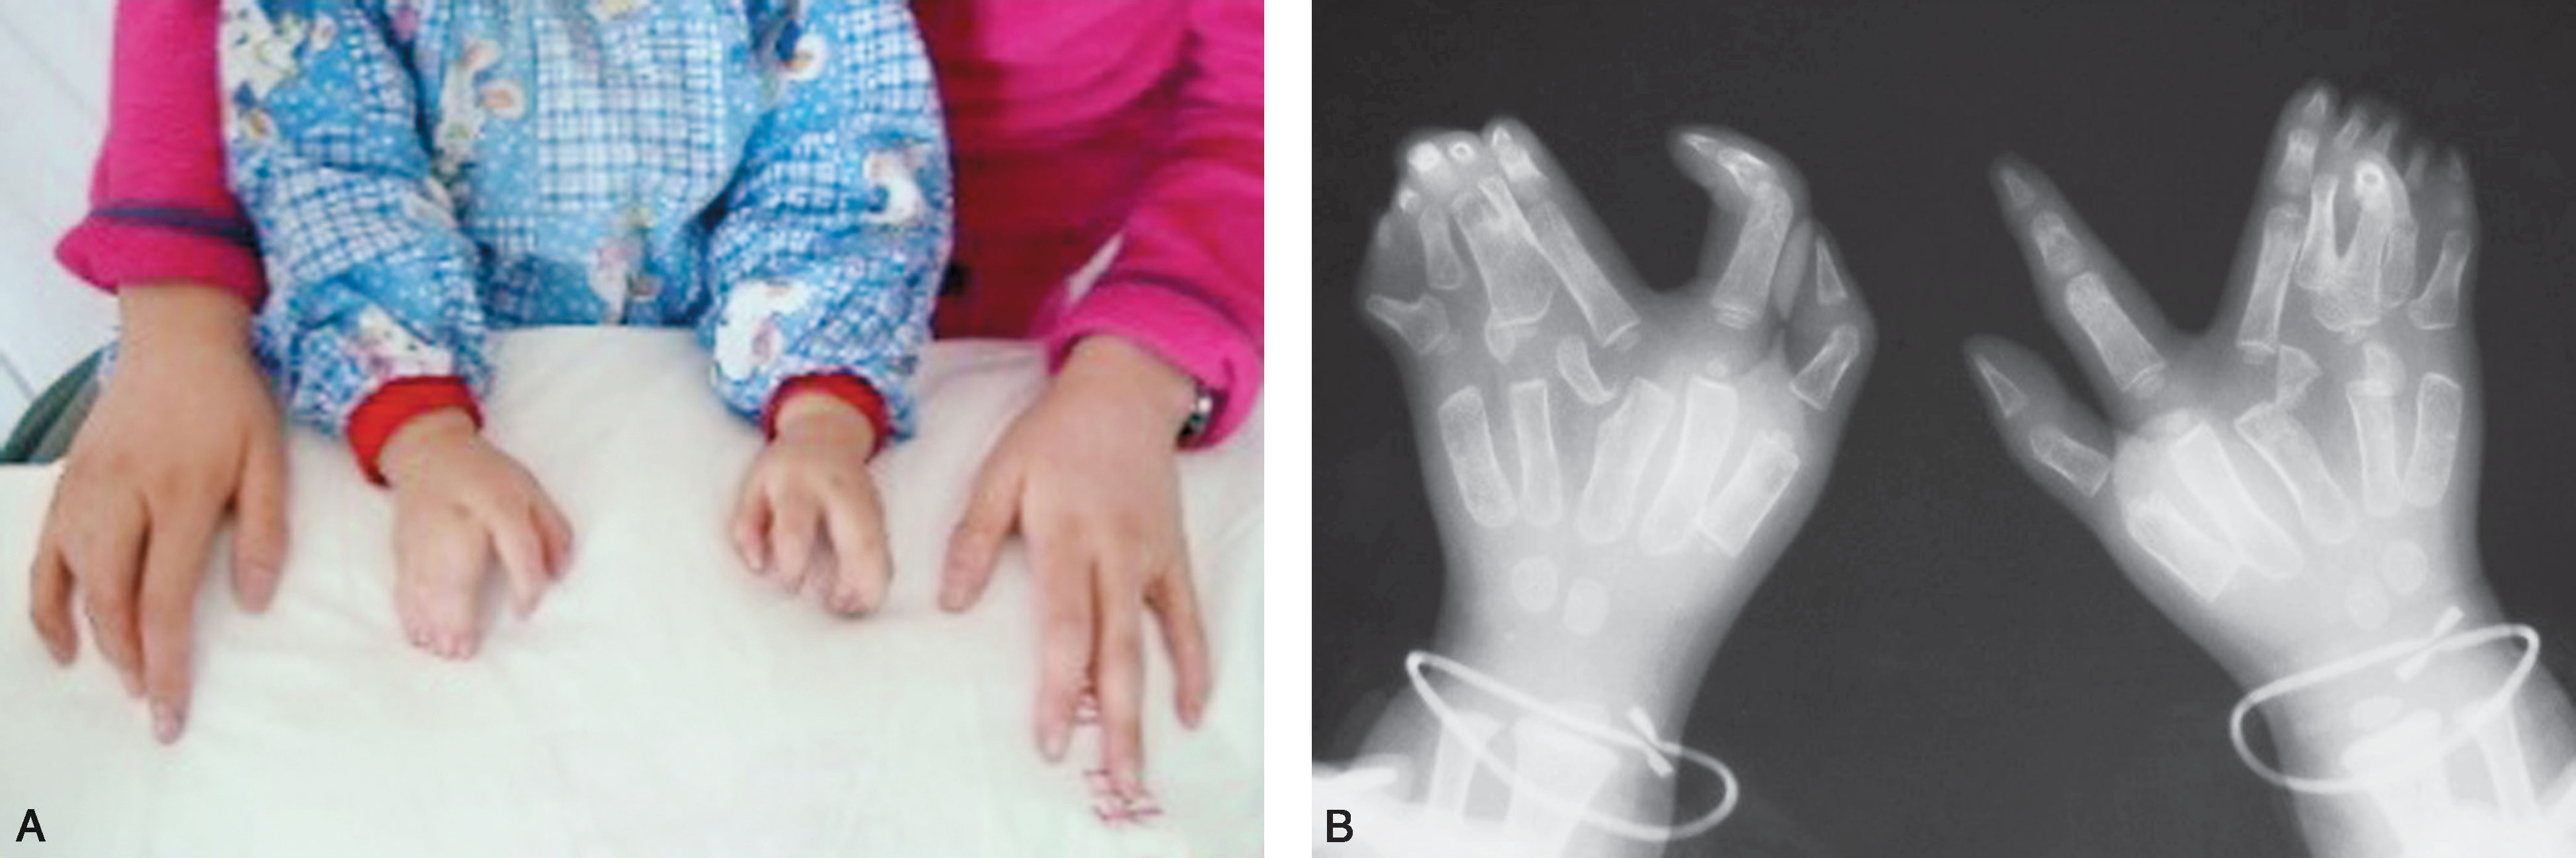

图2-5-5 桡侧与尺侧多指并存病例2

A.双侧桡尺侧多指同时存在(掌侧观),左小指漂浮指样多指,右小指肉赘样多指,双侧中环小指并指;B.背面观;C.双侧小指多指;D.双手X 线片显示骨关节畸形情况;E.同时合并足部多趾